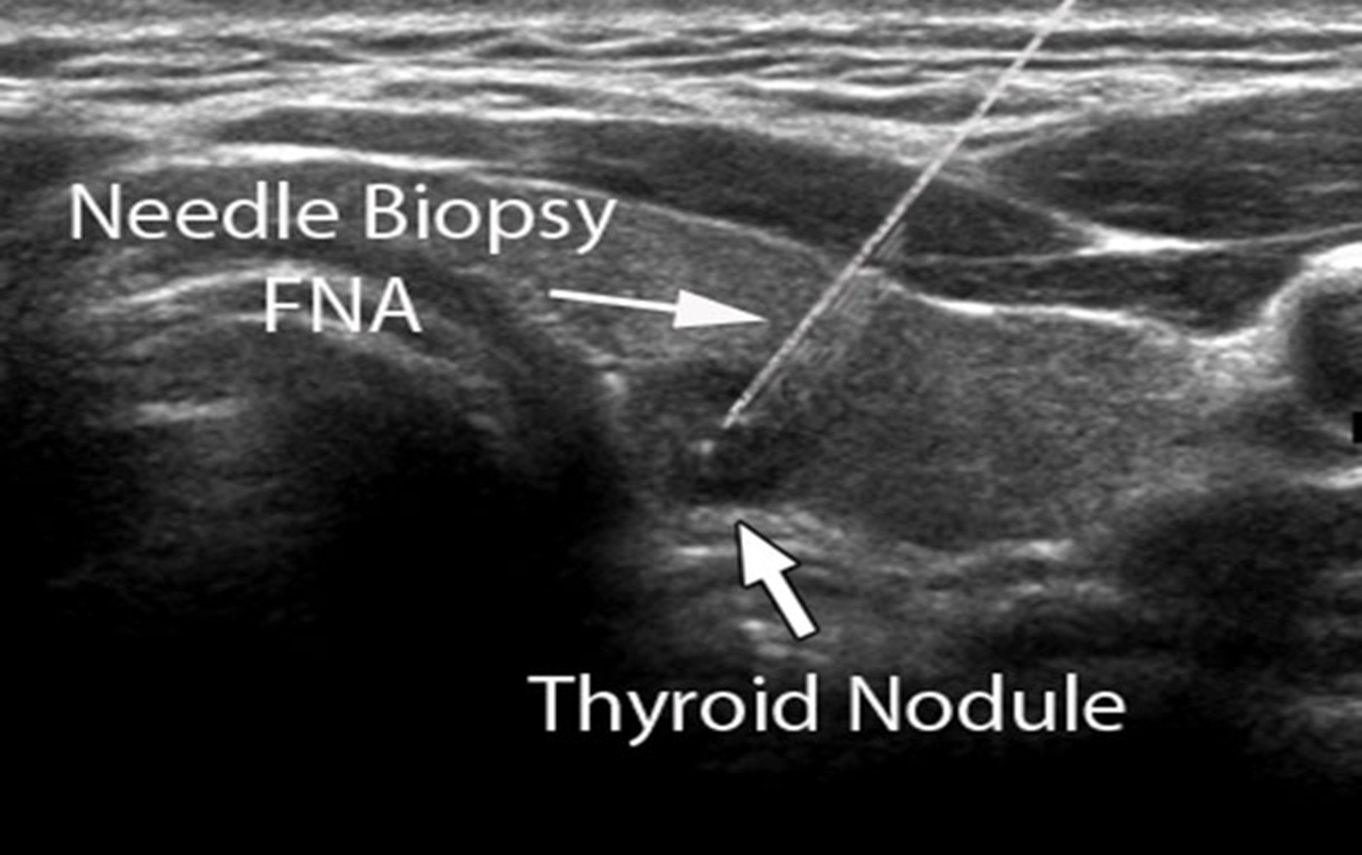

The use of FNA with cytological examination of the aspirate has become the mainstay of diagnosis of thyroid cancer.(US guided).

Ultrasound guided biopsy